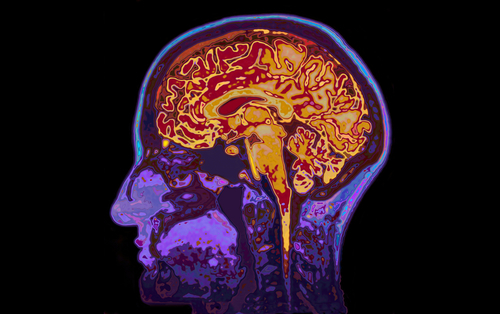

This study, in which researchers used functional magnetic resonance imaging (fMRI) to analyze brain activity, sheds light on why type 1 diabetics with hypoglycemia unawareness don’t respond appropriately by eating and then face dangerous drops in blood glucose levels.

The researchers gave all participants insulin to moderately lower their blood glucose levels and then conducted fMRI scans to observe the effects of hypoglycemia on brain activity. The brain scans showed that the three groups had dramatically different responses to lower blood glucose levels, even after adjusting for age and body mass index.

In participants without diabetes, mild hypoglycemia resulted in altered activity in the caudate, insula, prefrontal cortex, and angular gyrus—regions of the brain linked to reward, motivation, and executive control.However, T1DM participants with hypoglycemia awareness showed no changes in the caudate and insula, although they had altered activation patterns in the prefrontal cortex and angular gyrus.“Most strikingly, in direct contrast to healthy controls and T1DM-aware subjects, T1DM-unaware subjects failed to show any hypoglycemia-induced changes in brain activity,” Dr. Hwang and coauthors wrote.

“Hypoglycemia unawareness in T1DM patients is associated with a diminished brain response to mild hypoglycemia (plasma glucose ~60 mg/dl),” the authors concluded. “Moreover, the pattern of loss of brain responses appears to involve cortico-striatal and fronto-parietal neurocircuits that are known to play important roles in regulating motivation and goal-directed behavior, as well as attention.”

Dr. Hwang further explained, “There is a progressive loss of coordinated brain response to low blood sugar as you go from healthy adult to aware [diabetic] and unaware [diabetic]. The first areas in the brain to go are associated with regulating feeding behavior.”